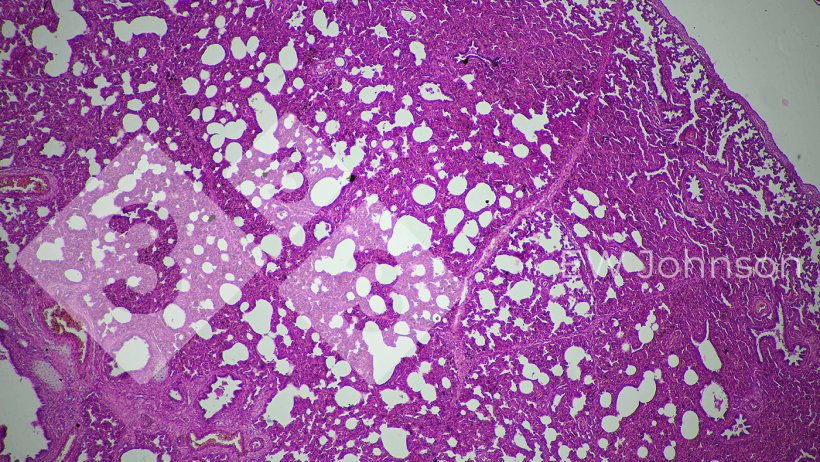

La PCR fue negativa a PRRS, pseudorabia (PRV, enfermedad de Aujeszky), circovirus porcinos PCV2 y PCV3, peste porcina clásica (PPC) y peste porcina africana (PPA). Se sabía que la granja estaba libre de PRRS, PRV, PPC y PPA antes de este evento. La PCR para Getahvirus en pulmón de lechón fue altamente positiva. La histopatología reveló neumonía intersticial grave (Figura 3) y meningoencefalitis fibrinohemorrágica (Figura 4). Se diagnosticó enfermedad perinatal por Getahvirus. Se informó a la granja de que esta enfermedad la transmiten principalmente los mosquitos y se aplicaron medidas de control. No se produjeron más casos ni signos clínicos en la granja y la producción volvió a su nivel normal.

Figura 3. La neumonía intersticial sugiere un posible origen vírico.